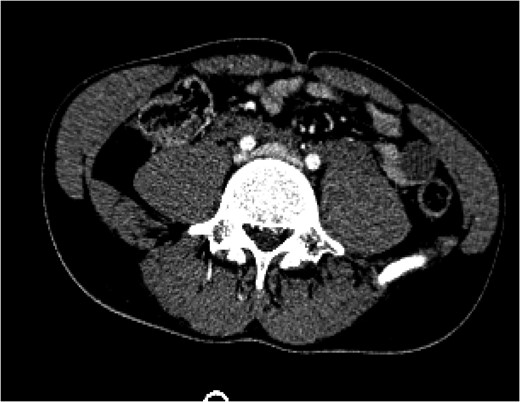

Figure 2:

An interventional radiology angiogram and venogram on Day 1 showed a 2.8 cm pseudoaneurysm in the proximal portion of the left common iliac vein. There was no involvement of the base of the IVC and no active extravasation.